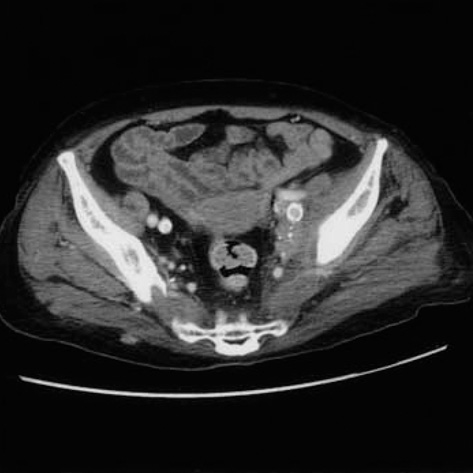

- Dermatomyositis (DM) is an uncommon inflammatory myopathy with characteristic rash accompanying, or more often preceding, muscle weakness. There is a well-recognized association between DM and several cancers, such as ovarian cancer, breast cancer, melanoma, colon cancer, and non-Hodgkin lymphoma. We report the first case of cancer of unknown primary site associated with DM. A 62-yr-old woman presented to us with both shoulder painful swelling and facial edema. She was diagnosed previously as cancer of unknown primary site, histologically confirmed with squamous cell carcinoma in a pelvic mass. For the following days, she complained of erythematous face followed by progressive weakness of the proximal muscles of upper and lower limbs. The laboratory tests showed an increased muscle enzyme and acute phase reactants. The electromyogram showed the typical findings of DM. After the treatment with high dose steroid and methotrexate, the proximal motor weakness improved, and she received palliative radiation therapy.

Figure